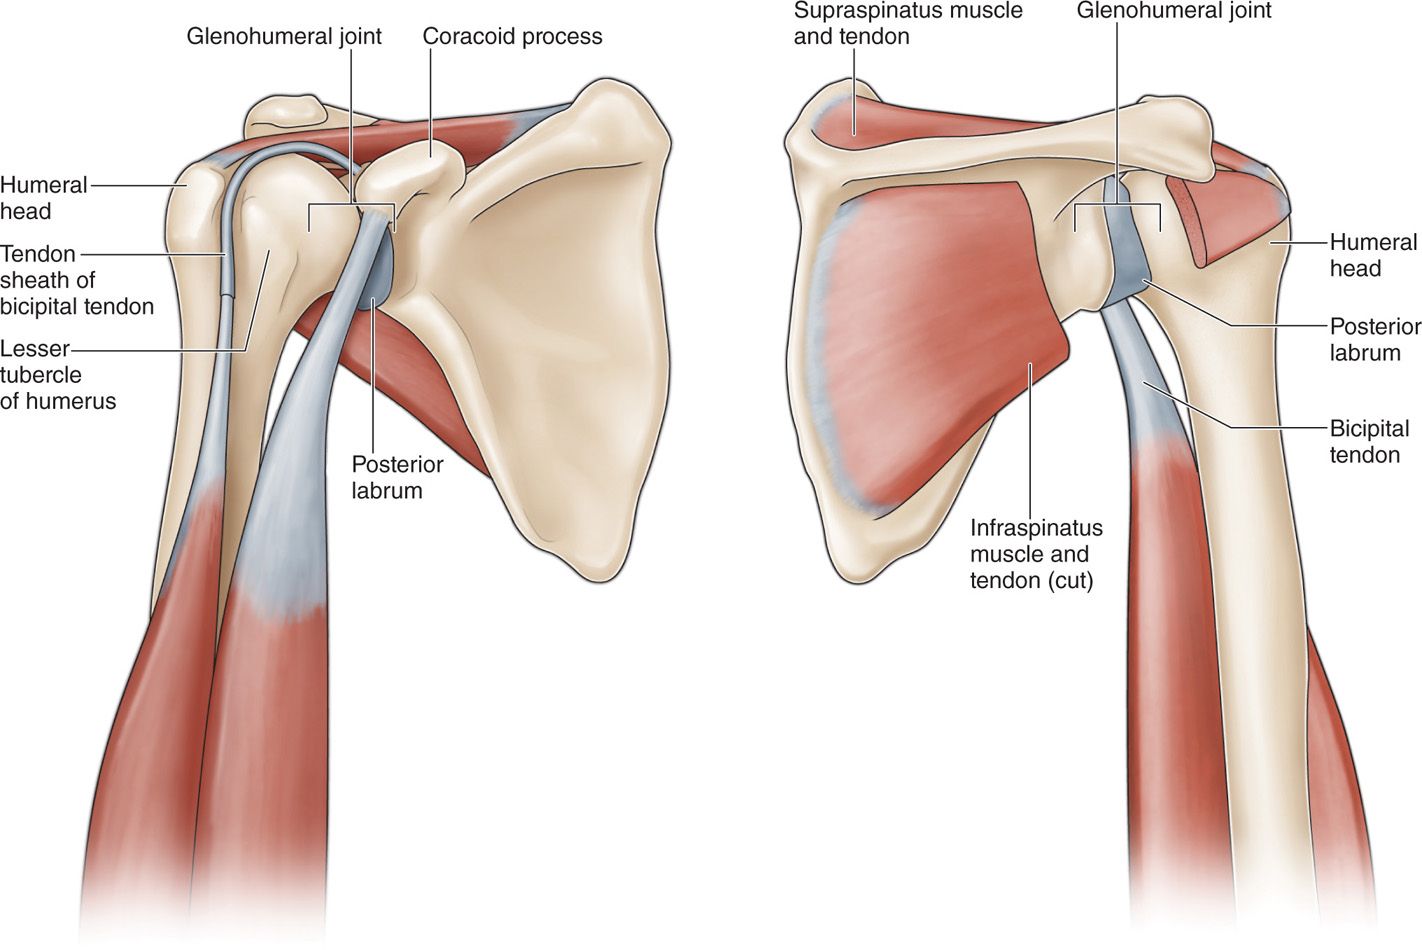

Glenohumeral ligament: анатомия и функции плечевого сустава